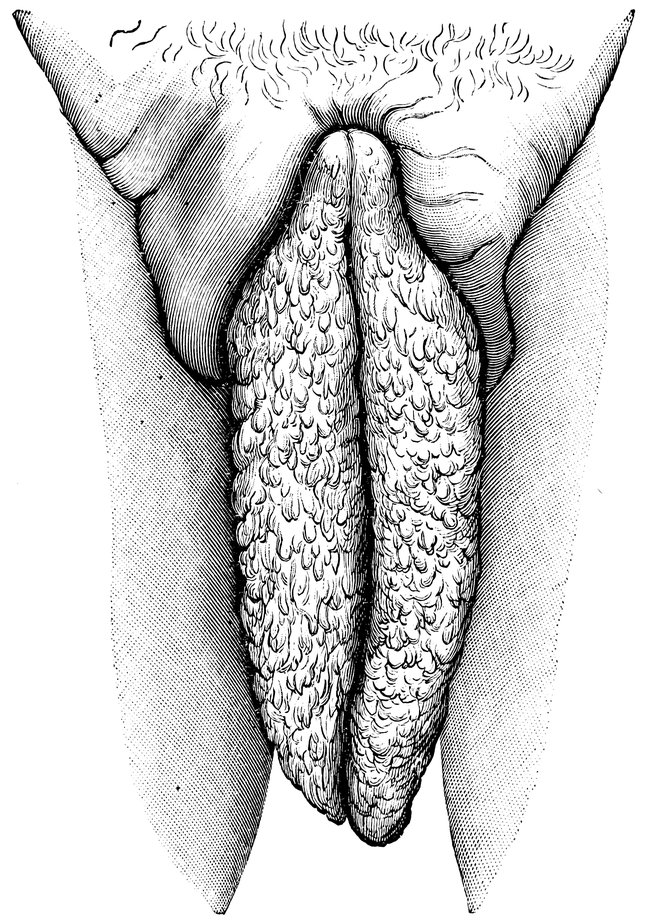

| 48. | The female pudendum, or vulva, with the labia majora | 204 |

| 68. | “Hottentot Apron” in an adult Woman, hanging down between the thighs (after Zweifel) | 329 |

| 69. | Elephantiasis of the Labia Majora | 330 |